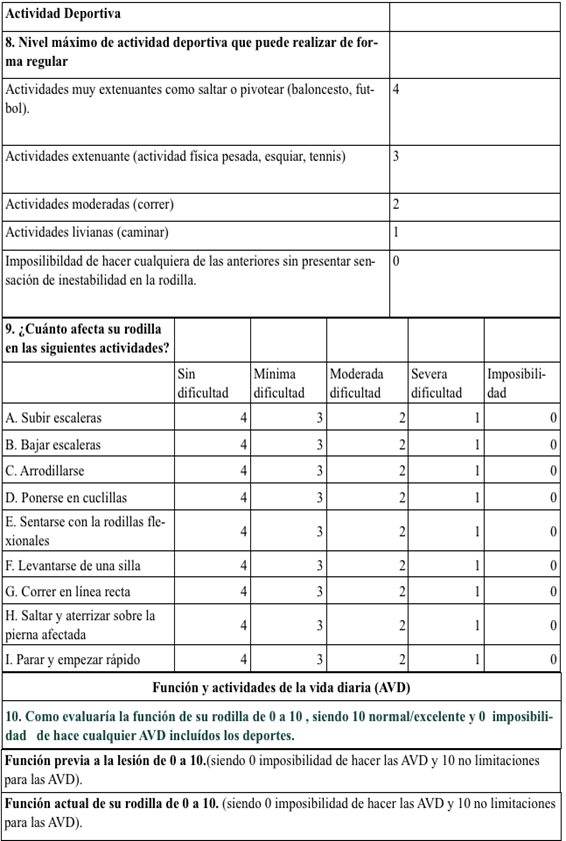

En sala de operaciones, con el paciente en decúbito dorsal bajo anestesia general, se colocó manguito neumático y un soporte para miembro inferior. Se realizaron los portales artroscópicos clásicos anteroexterno y anterointerno, visualizándose la lesión longitudinal del cuerno posterior del menisco interno y la rotura del LCA. Se procedió en primer lugar a la reparación meniscal. Una vez localizada la lesión, se testó la estabilidad del menisco con el probe, y se hizo un debridamiento con shaver del tejido fibroso. A continuación, se realizó un abordaje posteromedial mediante una incisión vertical en piel desde el tubérculo del aductor hasta el sector posterior del platillo tibial interno, sobrepasando 2cm la línea articular. En la disección profunda, se disecó la fascia del sartorio hasta observar el triángulo anatómico formado por: la cápsula (anterior), el gemelo interno (posterior) y el semimembranoso (inferior). Se llevó la rodilla a 20 grados de flexión y se colocó la cánula flexible en la cara superior de la lesión del menisco interno y usando material para pasar las suturas, se realizó la primera pasada de la aguja, recuperándose la misma con retractor posterior con la rodilla a 90 grados de flexión para evitar lesiones neurovasculares. Se prosiguió a la segunda pasada de la aguja en el sector de la lesión correspondiente, quedando ambos extremos del hilo por afuera, los cuales se anudaron. Se hicieron 2 puntos de sutura al menisco, comprobándose la estabilidad posterior a la reparación (Figura 2). A continuación, se pasó a realizar la plastia de LCA. Se realizó un debridamiento previo de los restos de LCA. Se amplió distalmente abordaje posteromedial, para exponer la inserción de los isquiosurales, y se obtuvo injerto de pata de ganso. Se observó huella del LCA a nivel del fémur, y se realizó el túnel de 8mm. A continuación se coloca guía para túnel tibial, realizándose el mismo. Se colocó el injerto y se fijó próximalmente con endobuttom, y distalmente con tornillo de interfrencia de titanio 7X20mm con la rodilla en flexión de 30 grados y realizándose cajón posterior (Figura 3). Se verificó la estabilidad anterior intraoperatoria, se realizó el cierre por planos y un vendaje elástico del miembro. Los controles se realizaron de la siguiente manera: a los 15 días, a las 6 semanas, a los 3 meses, a los 6 meses, al año y a los 2 años.

Figura 2. Imágenes del intraoperatorio de la reparación inside out del menisco interno. A y B. Vista artroscópica que evidencia la lesión meniscal interna y rotura del LCA respectivamente. C. Abordaje posterointerno desde el tubérculo del aductor hacia platillo interno. D. Colocación del retractor posterior con rodilla a 90 grados evitando lesiones neurovasculares. E y F. Primer punto de sutura. G. Ayudante recuperando la aguja. H e I. Segundo punto de sutura. J. Se comprueba estabilidad posterior del menisco.